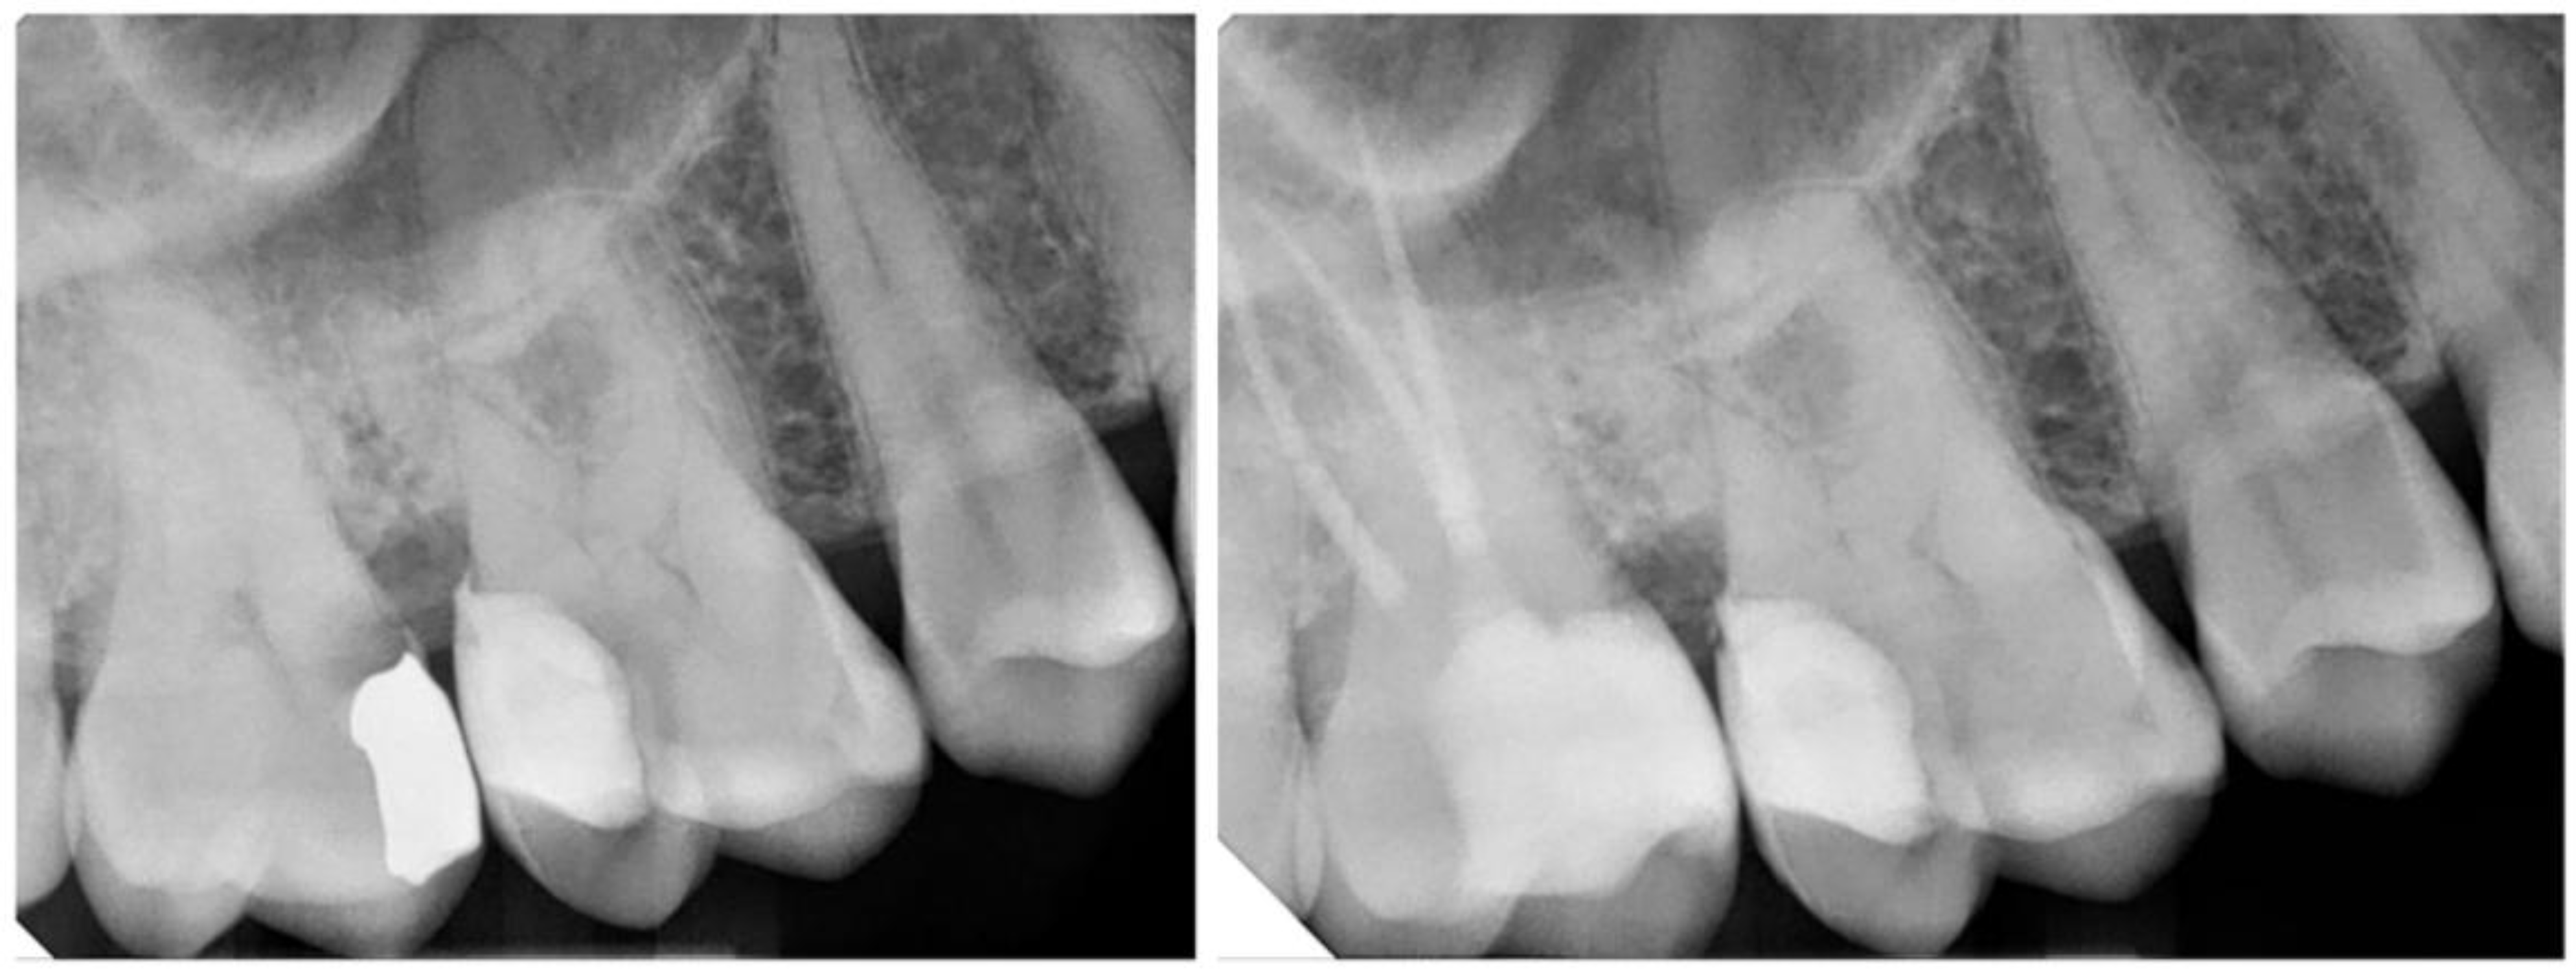

Figure 8.

(left) Subgingival margin with deep STA violation. In such cases, crown lengthening should be considered. (right) Subgingival margin with minor STA violation. In such cases, DME can be tolerated in such cases.

The relationship between DME and periodontal health has long been a topic of debate, with heterogeneous results in the literature. It is generally accepted that DME is contraindicated when the cervical margin is located less than 2 mm from the bone crest; in such instances, surgical crown lengthening should be considered (Figure 7 and Figure 8). Before determining the treatment plan, clinicians should carefully assess the distance from the bone crest through radiographic examination and bone sounding. When the supracrestal tissue attachment (STA) is preserved (more than 2.04 mm from the bone crest), DME can be compatible with periodontal health, provided that the patient maintains adequate oral hygiene (Figure 9). It is essential to establish an emergence profile that enables the patient to maintain effective oral hygiene. Undercontoured profiles and STA violation may result in open contact points, food traps, gingival inflammation, and ultimately, restoration failure (Figure 10). Additionally, the stages of excess removal, finishing, and polishing of the composite are critical, as only a perfectly smooth composite surface can facilitate the formation of a healthy junctional epithelium, thereby promoting periodontal health [25].